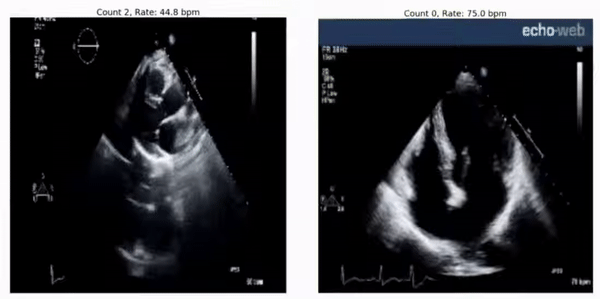

RepNet 可用于评估来自超声波心动图视频的心率,即便它在训练期间并未见过这样的视频:

预测心率: 45 bpm(左)和 75 bpm(右)。 实际心率分别为 46-50 bpm 和 78-79 bpm。 RepNet 对不同设备的心跳速率预测非常接近设备实际测得的心跳速率